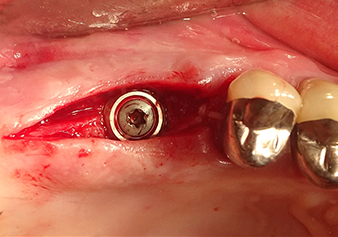

Following an intermediate check (Fig. 4) a further preparation step was performed (Fig. 5). Afterwards, the hydraulic Z35P instrument was used to lift the membrane to the desired position (Fig. 6 and 7). This was followed by further piezosurgical preparation of the implant bed, concluded with a rotary bur and shoulder milling cutter up to the implant diameter of 4.8 mm. Before the implant was inserted, the augmentation material (particle size approx. 0.8-1.6 mm) was introduced underneath the Schneiderian membrane (Fig. 8).

To move the augmentation material in the direction of the maxillary sinus atraumatically, the implant was inserted very slowly by hand (Fig. 9). In the process, the membrane was pushed in the cranial direction once again. After two months, the surgical site healed without irritation. Six months later, the x-ray check showed a significant increase in opacity as an indication of ossification (Fig. 10). The prosthetic restoration was carried out with a metal-ceramic crown.

Situation after insertion of the implant

Fig.9: Situation after insertion of the implant (length: 10 mm, prosthetic platform: 6.5 mm) immediately before suturing.